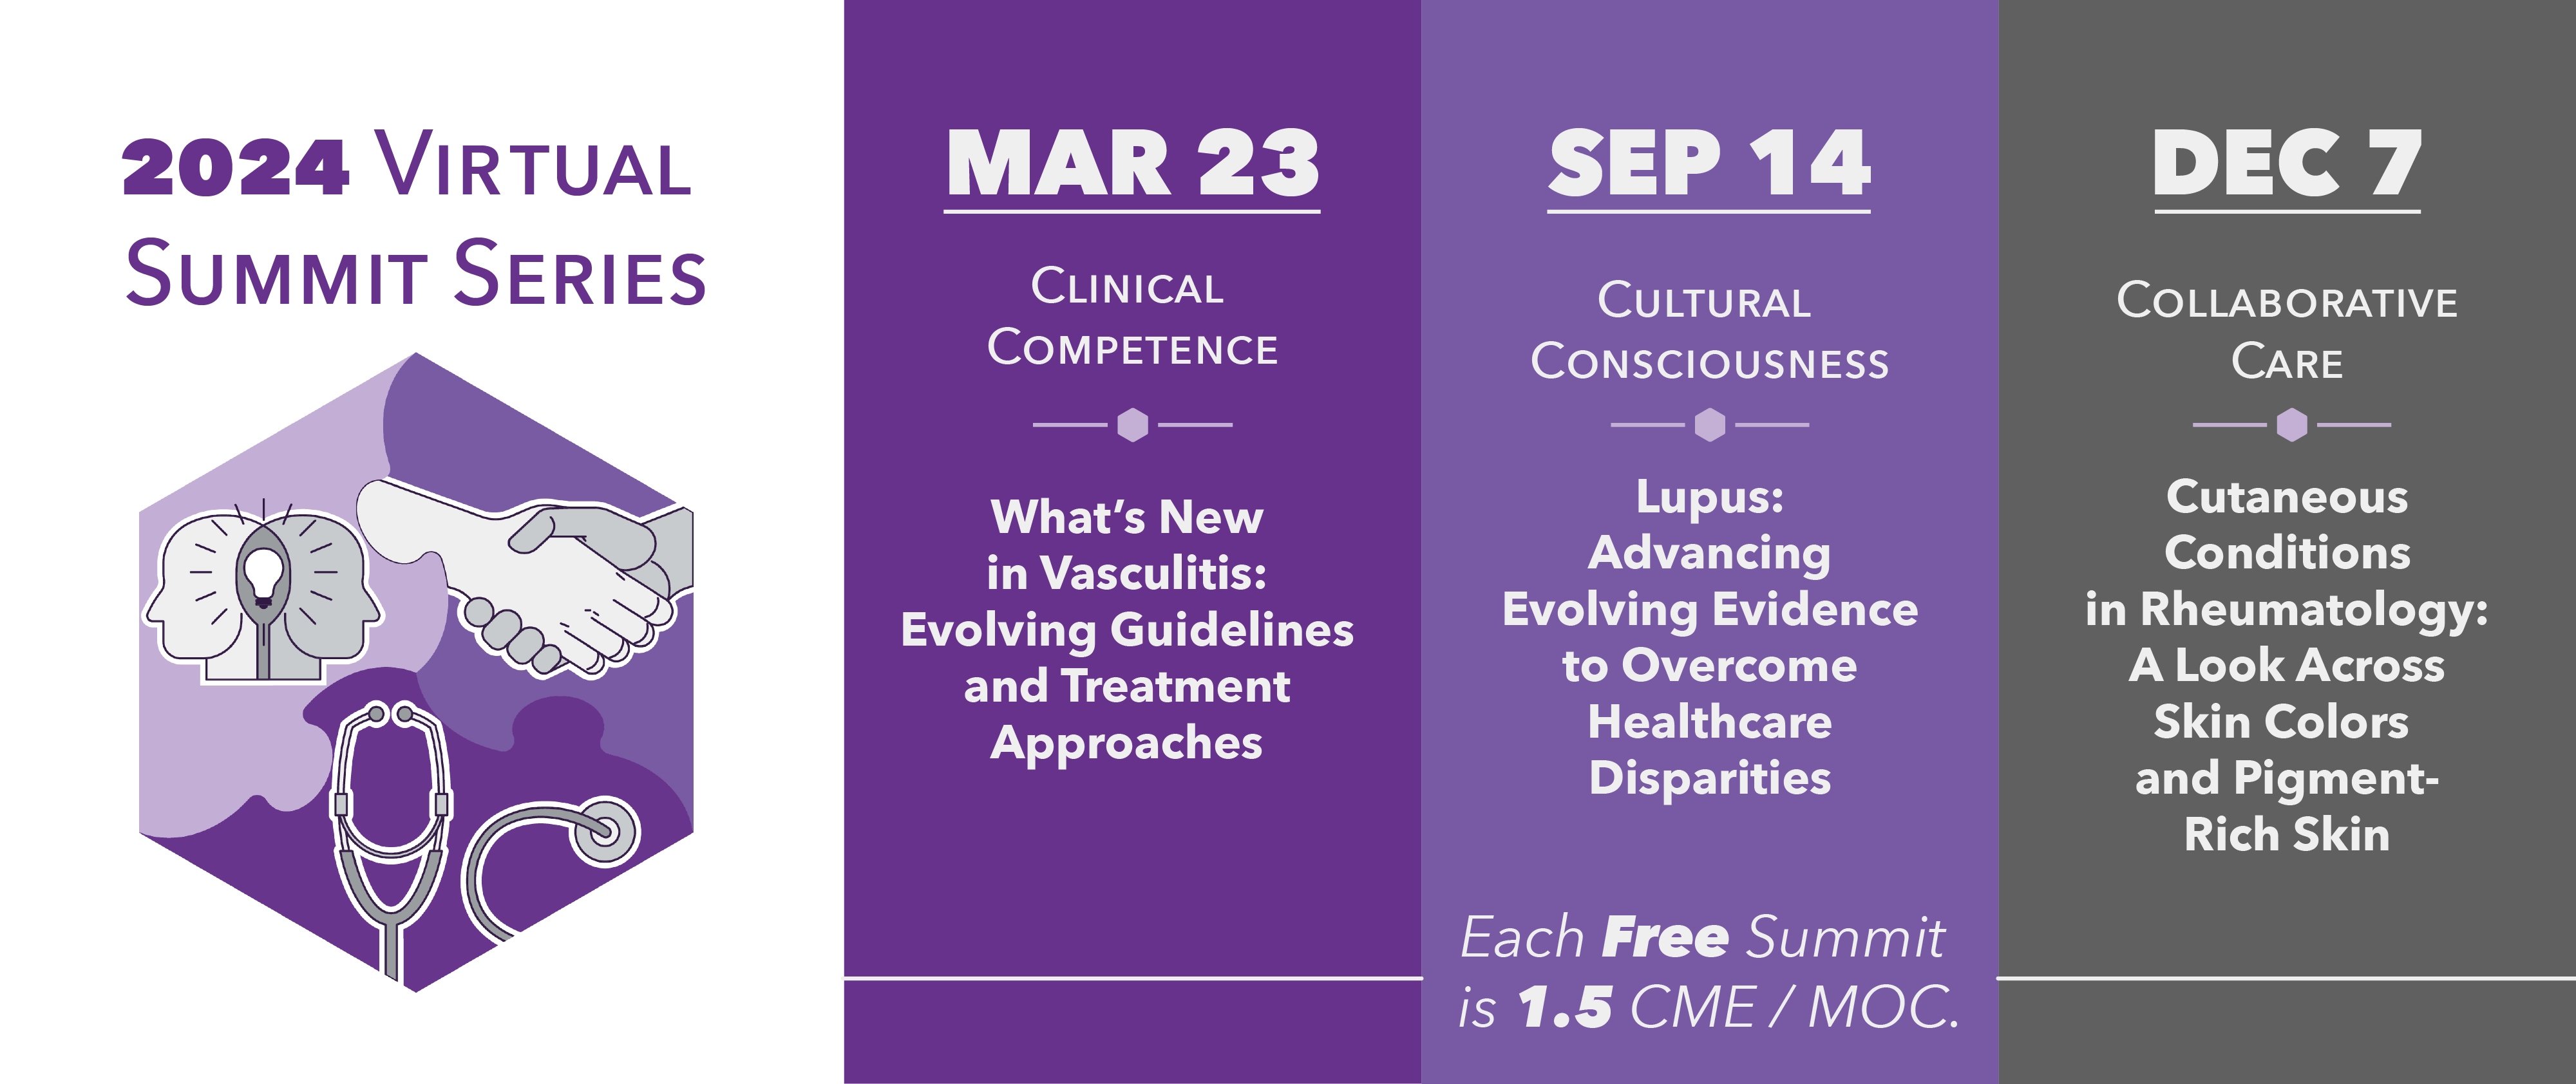

- AWIR Summits are always free and open to everyone in the Rheumatology community, both in the U.S. and ex-US! Each year, hundreds of participants join us from more than 20 countries to hear from leading experts and industry partners about the latest advances in the treatment and management of rheumatic diseases. Plus, you can earn free CME/MOC credits to meet your license requirements! Most importantly, our Summits are a way to meet and network with colleagues through Watch Parties hosted by many of our Local Chapters! Connect with your Local Chapter Leader to find out more.

Registration is required. There is no cost to attend.

AWIR Summits will be offered virtually with local community Watch Parties

Sep 14

Lupus: Advancing Evolving Evidence to Overcome Healthcare Disparities

Location: Virtual with Community LocationsTime: 12:00 pm- 3:00 pmClick here to register

Dec 07

Cutaneous Conditions in Rheumatology: A Look Across Skin Colors and Pigment-Rich Skin

Location: Virtual with Community LocationsTime: 12:00 pm- 3:30 pmClick here to register

In our summits, our expert speakers and engaging sessions will equip our attendees with the skills and knowledge necessary to align their practice with evolving evidence, so they are better prepared to provide optimal and equitable care for all their patients with rheumatic conditions.